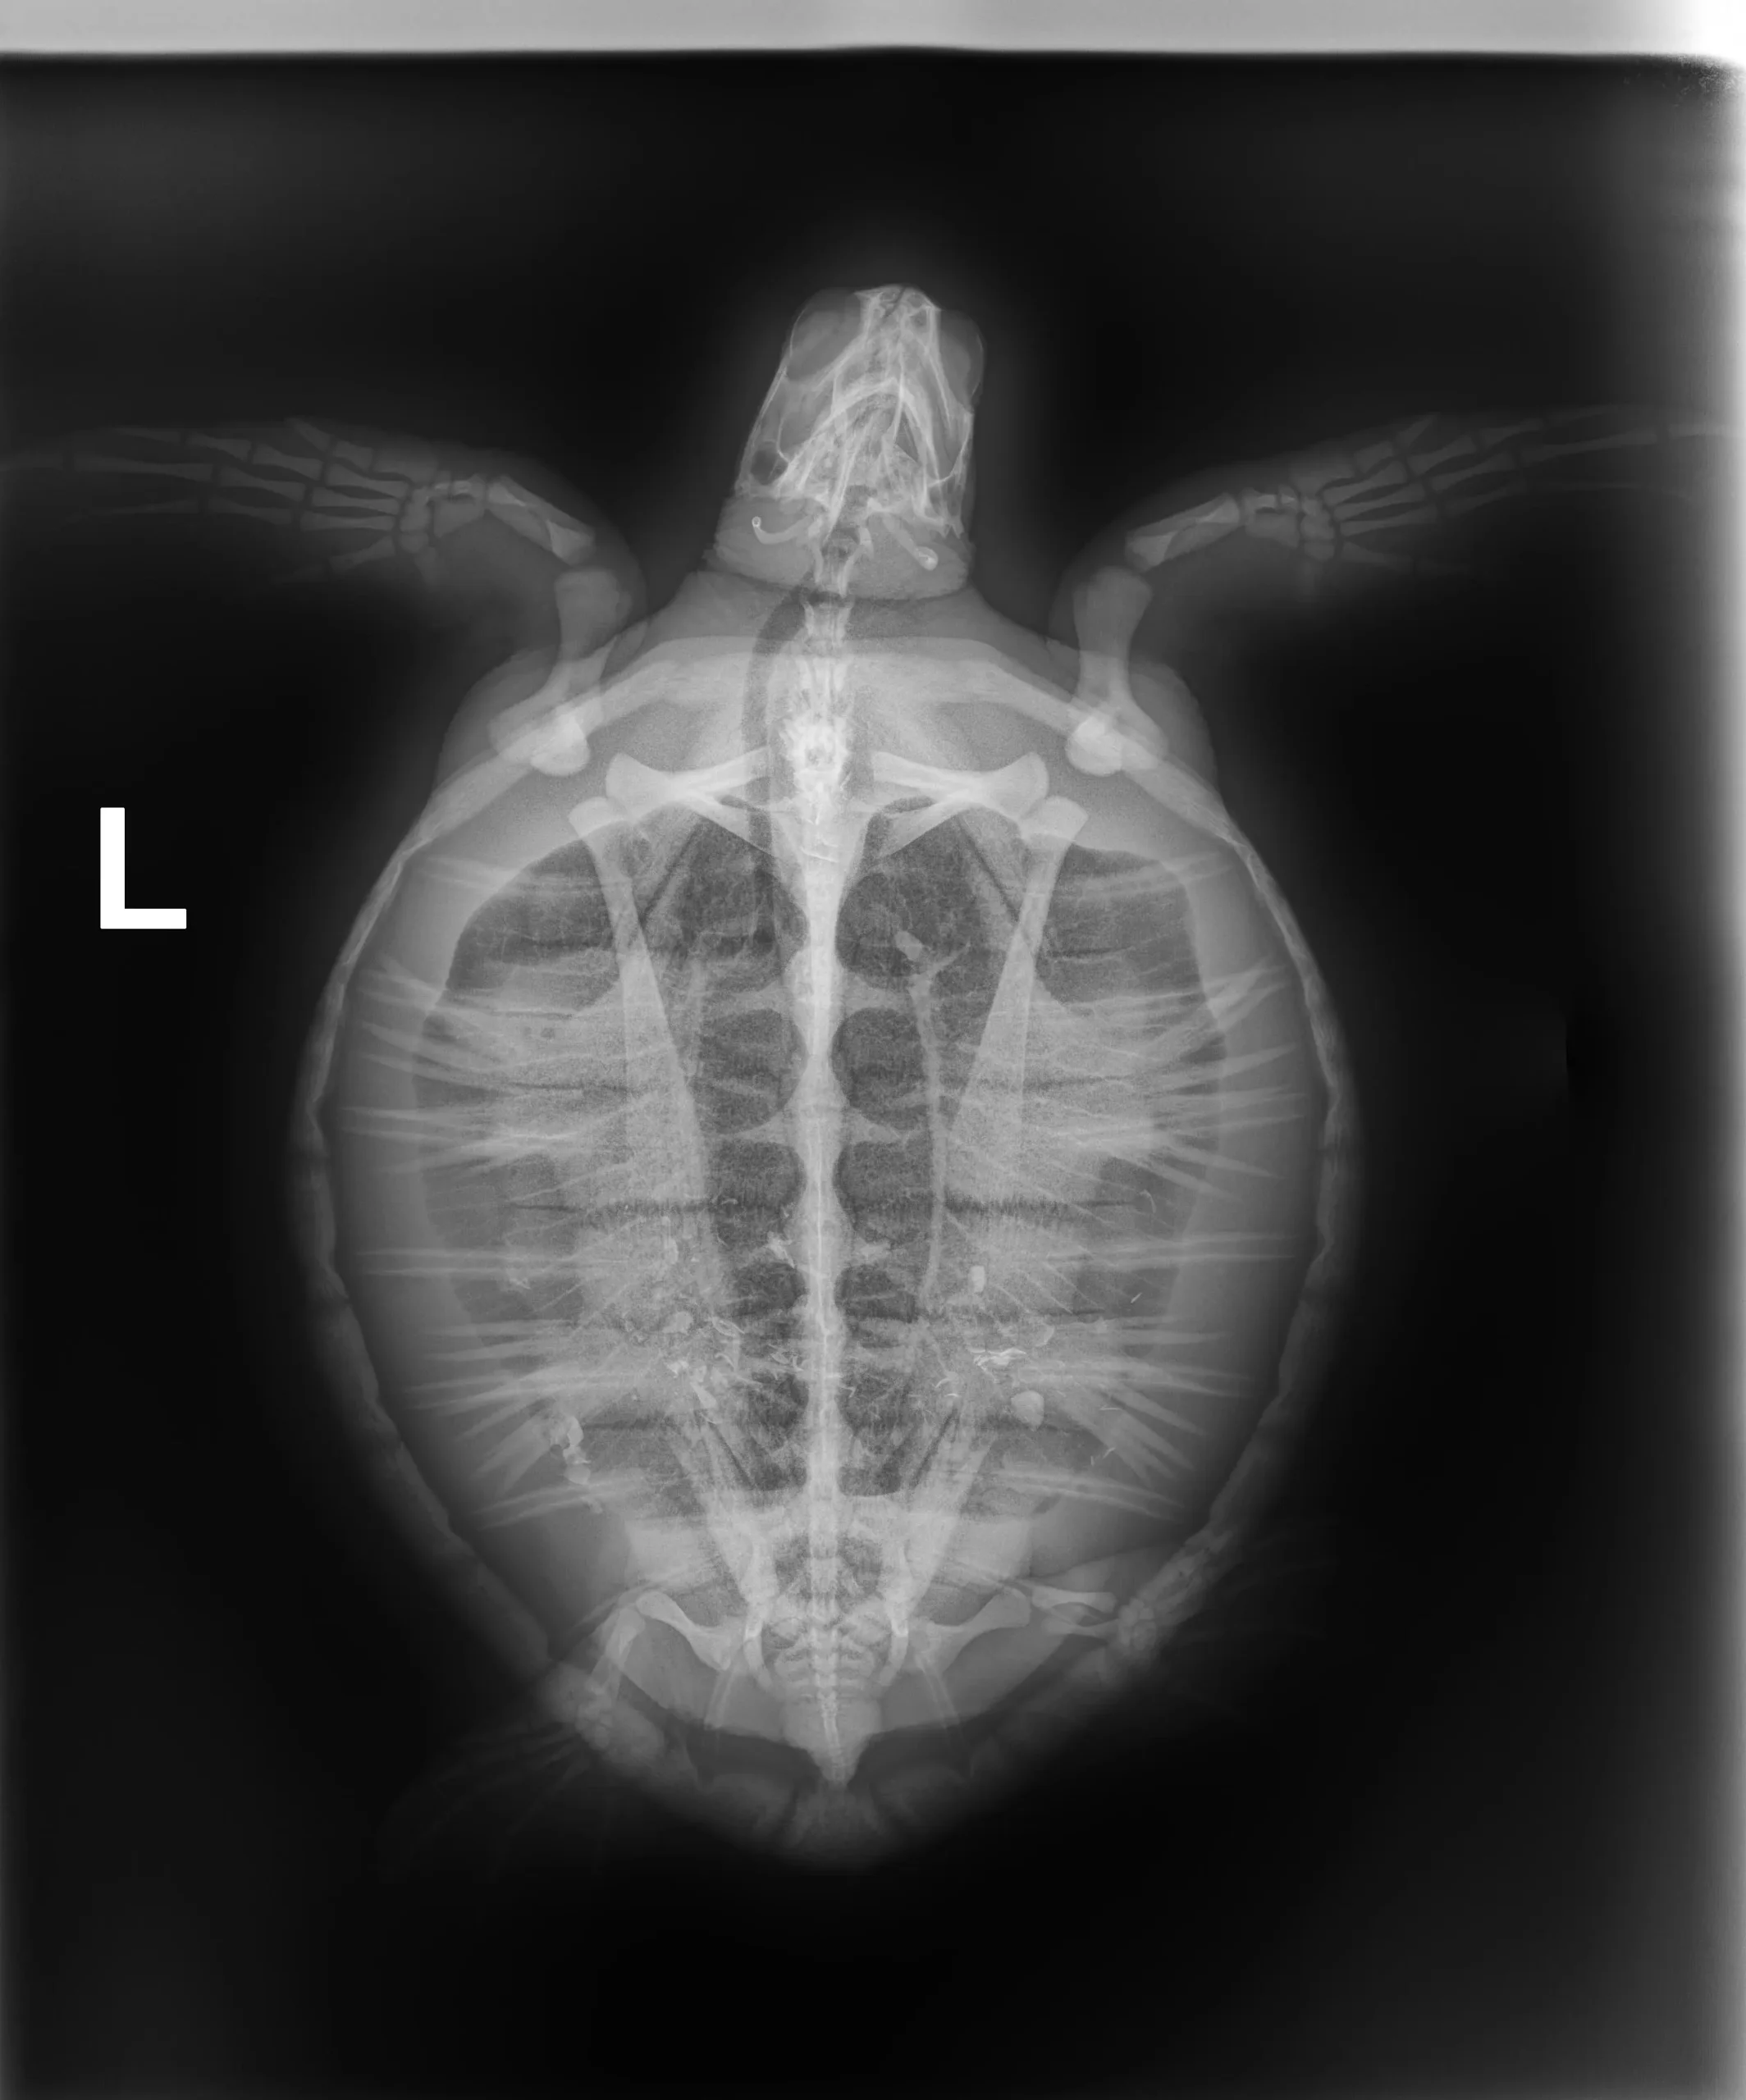

4.6 lbs. non-FP juvenile green

Minor abrasions on plastron

In-house PCV = 34%, TP = 3.4 g/dl, glucose = 90. Started on Ceftazidime, Vit B Complex, and Normosol.